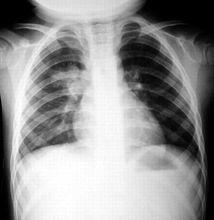

也有生後數月進進展為慢性肺炎,周圍血象白細胞大多正常,也可減少或增加。血清IgM,IgA比正常新生兒高,臍血IgM>200mg/L或特異性IgM增高者對產前感染有診斷意義。X線胸片常顯示為間質性肺炎改變,細菌性肺炎則為支氣管肺炎表現。生後1~2小時檢查胃液,見膿細胞,有時可找到細菌。外耳道咽拭子細菌培養可陽性。

(四) X線表現: 肺內廣泛粟粒狀陰影或片狀陰影,有時伴有肺的過度充氣或肺氣腫。